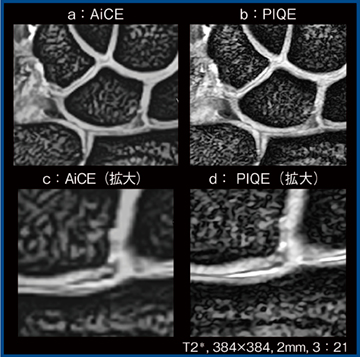

骨間靭帯が破綻すると,dorsal intercalated segment instability(DISI)やvolar intercalated segment instability(VISI)と呼ばれる手根骨のアライメントの異常を来し,機能障害を生じるため,骨間靭帯やアライメントの早期の画像評価が重要となる。図2は,骨間靭帯断裂および関節軟骨損傷の症例である。従来画像(AiCE適用:図2 a)でも十分な所見が得られるが,PIQE(b)では,TFCCの断裂し退縮した円盤部の不整や,尺側靭帯の付着部のたわみ,関節軟骨の不整,舟状骨・月状骨間靭帯の断裂,月状三角骨間靭帯の欠損が,より明瞭に観察できる。また,マトリックス数を384に上げた撮像(図3 a,b)では,PIQEにて舟状骨・月状骨間靭帯の断裂の断端部の性状や関節軟骨損傷がより詳細に評価可能であった。さらに,別のスライスの拡大像(図3 c,d)を見ると,月状骨の靭帯付着部近傍の関節軟骨損傷の領域が,PIQEでは損傷と,部分的に残存する関節軟骨の領域を分離して同定可能であった。

図3 図2と同一症例におけるマトリックス数を上げた画像の比較